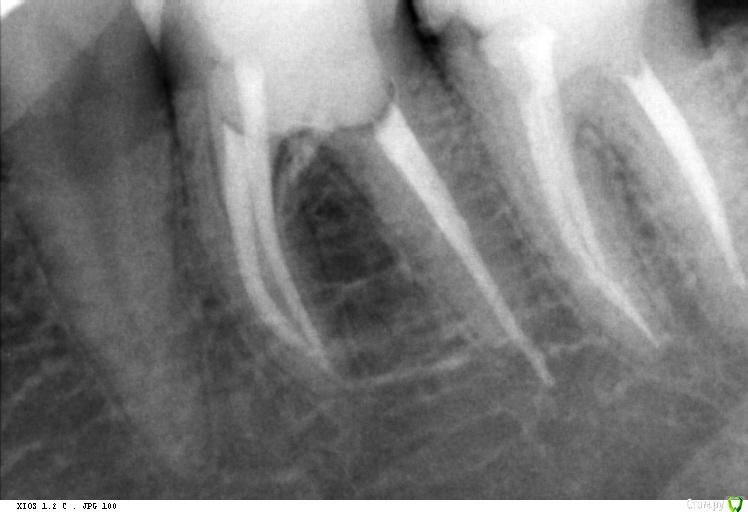

Vords Опубликовано 12 июня, 2020 Автор Поделиться Опубликовано 12 июня, 2020 Да прицельный качественный подтвердит наличие штифта за апексом Доброго дня! Сделал прицельный еще один. По нему можно сделать какие-то выводы относительно наличия штифта? Благодарю за уделенное время. Ссылка на комментарий

krokomot Опубликовано 12 июня, 2020 Поделиться Опубликовано 12 июня, 2020 Да есть 2 Ссылка на комментарий